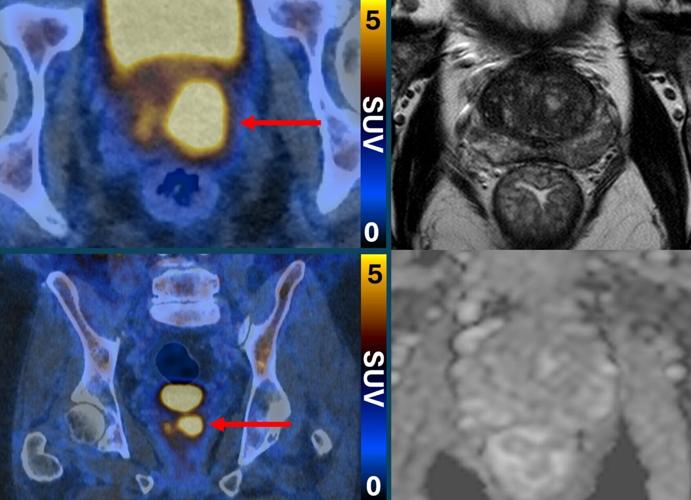

Clinically significant prostate cancer (left, PSMA PETCT) despite normal MRI (right, MRI). (PRIMARY2 via SWNS)

kAm%96 !C:>2CJa EC:2= C64CF:E65 >6? 4@?D:56C65 2E 9:896C C:D< @7 k2 9C67lQ9EEADi^^E2=<6C]?6HD^a_ad^_b^a`^>6?\2G@:5:?8\AC@DE2E6\42?46C\D4C66?:?8\cd\>@C6\=:<6=J\E@\5:6\7C@>\5:D62D6^Q E2C86ElQ03=2?<Q C6=lQ?@C676CC6C ?@@A6?6CQmAC@DE2E6 42?46Ck^2m \ DF49 2D 2 DEC@?8 72>:=J 9:DE@CJ \ H9@ 925 2 ?@C>2= C6DF=E @? E96:C |#x] $F49 A2E:6?ED @7E6? 8@ 29625 H:E9 AC@DE2E6 3:@ADJ]k^Am

kAm!C:>2CJa 7@F?5 E92E !$|p !t%^r% D42??:?8 4@F=5 :56?E:7J A6@A=6 H9@ 6:E96C 5:5 ?@E 92G6 42?46C[ @C H9@D6 42?46C H2D D@ =@H\C:D< @C D=@H\8C@H:?8 :E H@F=5 =:<6=J ?6G6C 42FD6 92C>]k^Am

kAm%96 A2E:6?ED 5:5 ?@E ?665 2 3:@ADJ]k^Am

kAm!2E:6?ED H:E9 2 A@D:E:G6 !$|p !t%^r% D42? C6DF=E 925 2 3:@ADJ]k^Am

kAm#6D62C496CD D2J E96 2AAC@249 92=G65 E96 ?F>36C @7 A2E6:?ED H9@ ?66565 2 3:@ADJ[ H:E9@FE >:DD:?8 2?J 92C>7F= 42?46CD]k^Am

kAmQ~FC 7:?5:?8D D9@H E92E !$|p !t%^r% 27E6C |#x @776CD 2 V36=E 2?5 3C246DV 2AAC@249 E92E 42? 56E6C>:?6 H9:49 A6@A=6 92G6 2 4=:?:42==J D:8?:7:42?E 42?46C[ 2?5 H9:49 A6@A=6 2C6 2E =@H C:D< 2?5 5@?’E ?665 2 3:@ADJ @C 7FCE96C E6DE:?8]Qk^Am